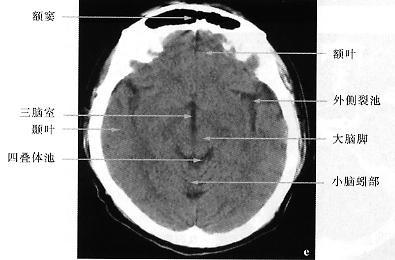

颅脑ct解剖图谱

颅脑横断面ct解剖图

颅脑ct八个层面清晰图

正常颅脑ct解剖层面